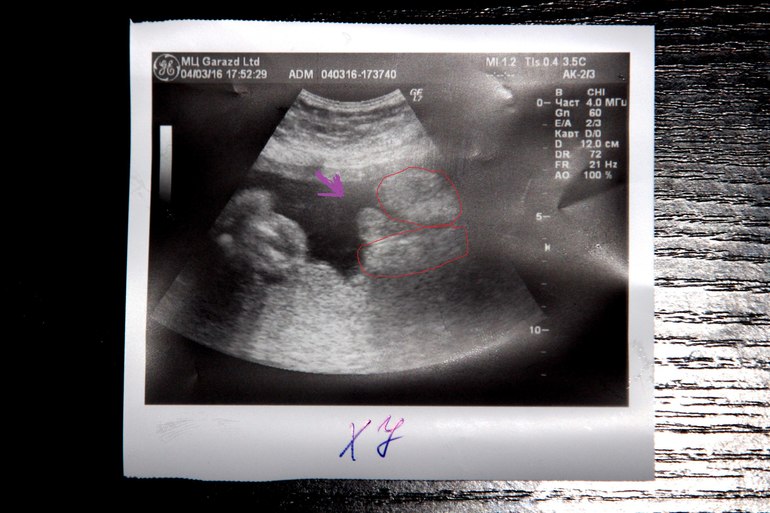

вот так у нас было видно! обведена одна и вторая булочка,а между ними как сказал узист яички)))))